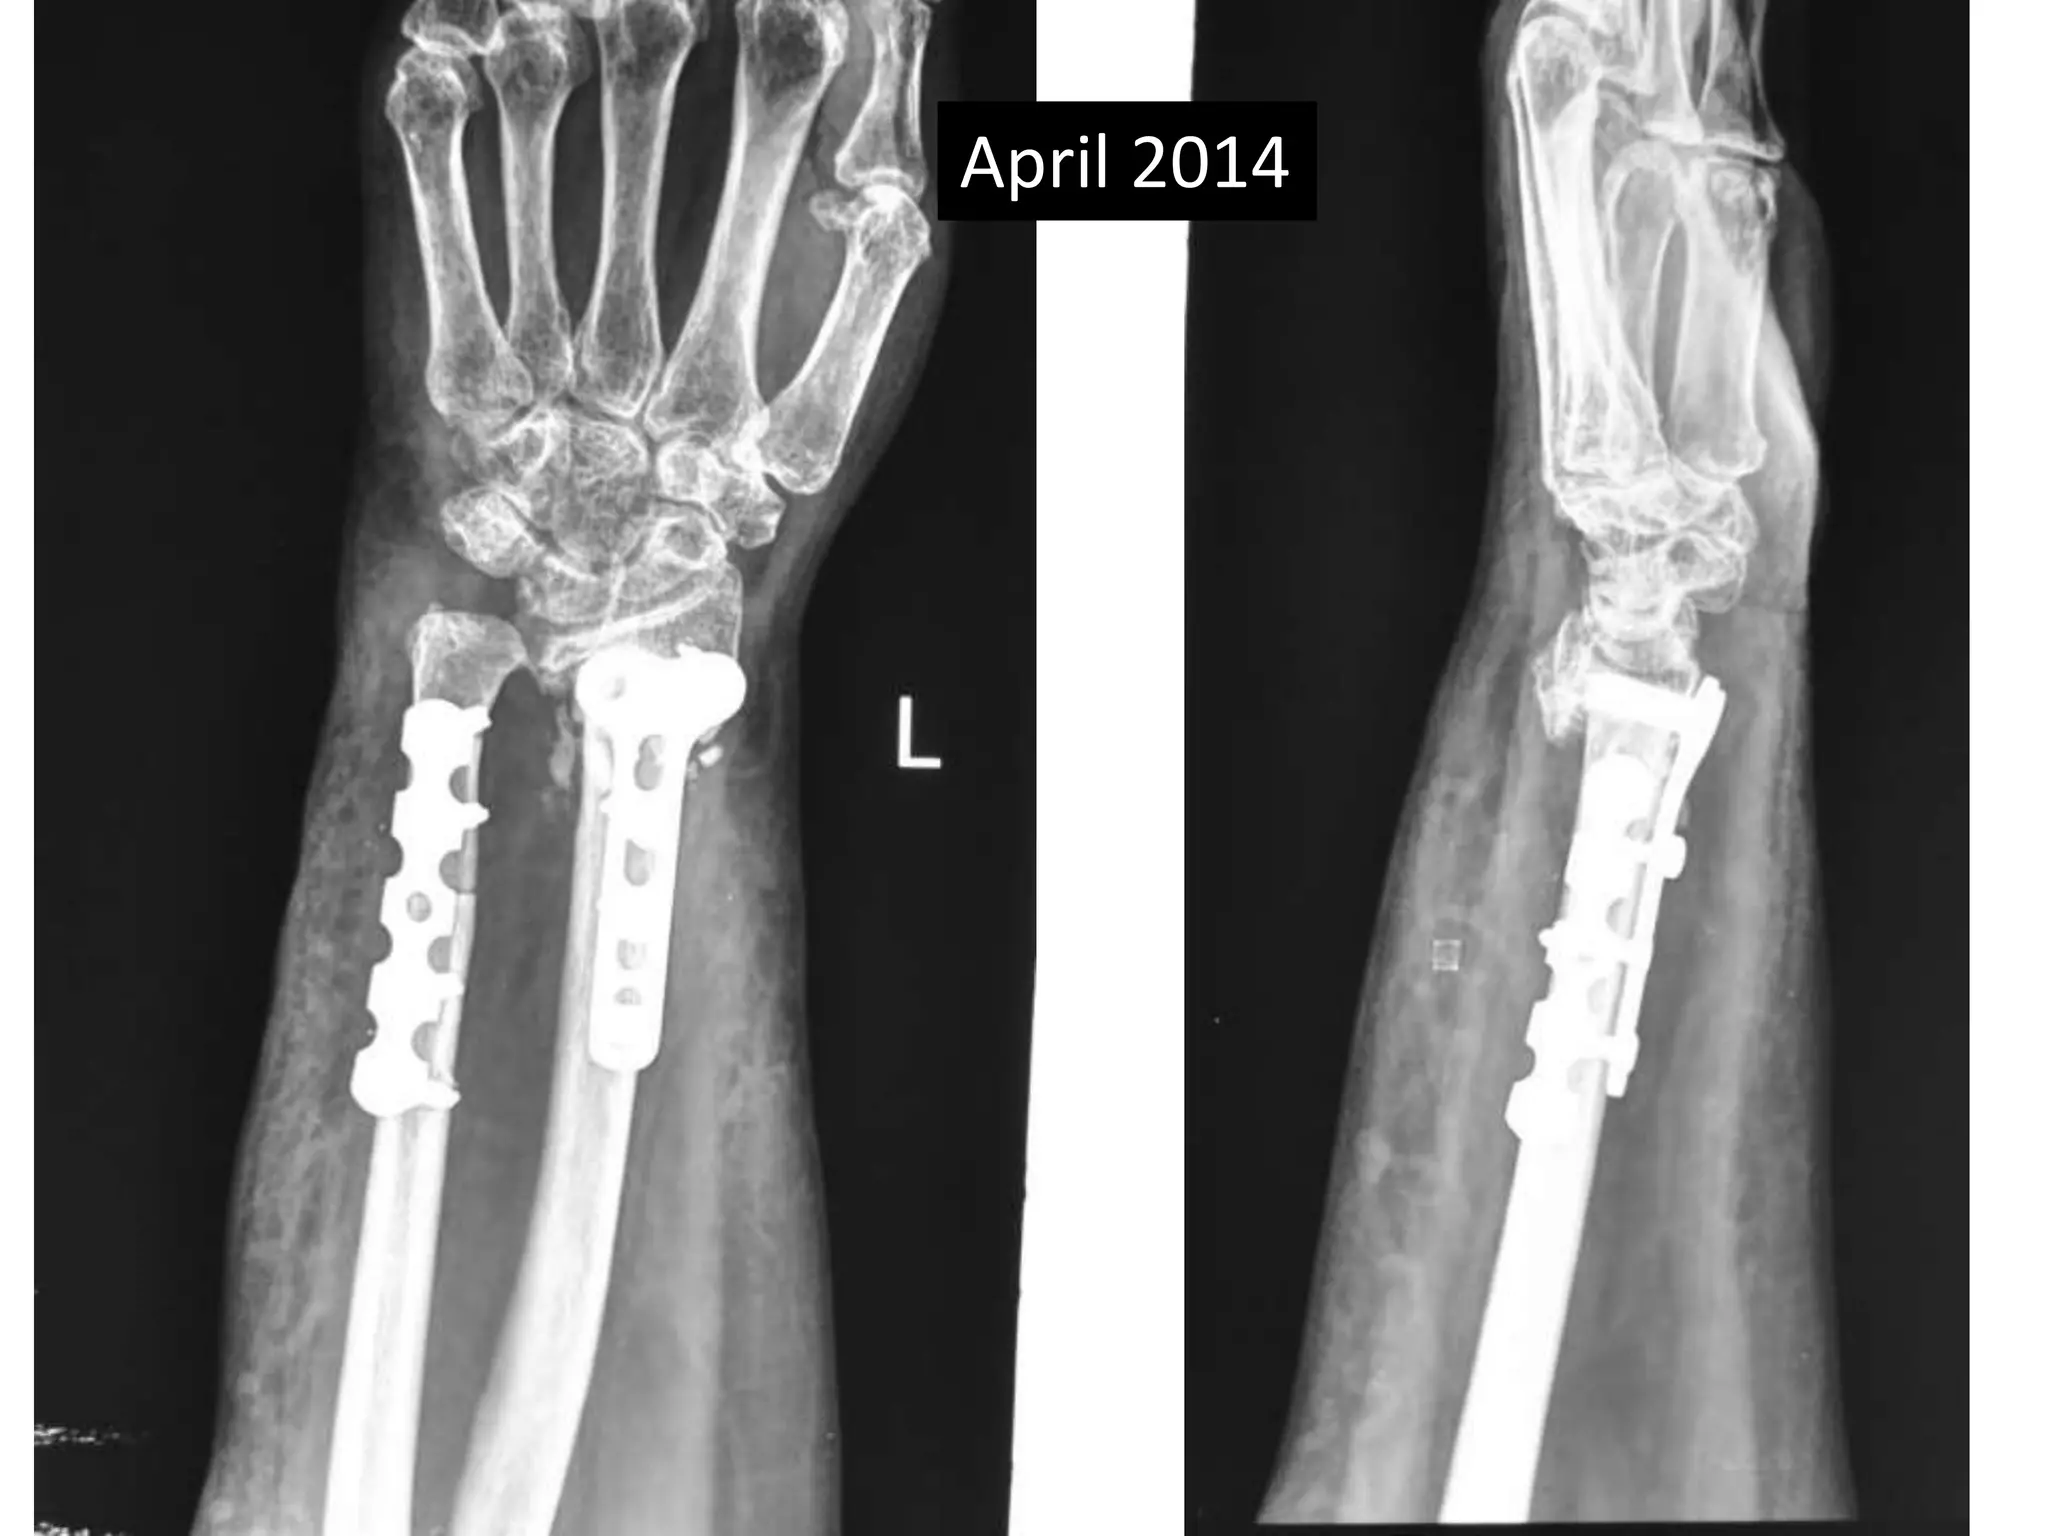

April 2014

Case two •50 years old female • Low energy injury • Sustained fracture lower end radius • Pop cast for six weeks • Progressively increasing deformity following removal of plaster. • X- rays after six months following fracture showing non-union.

Surgery • Volarexposure • Removal of scar tissue and clearing of bone ends. • Release of soft tissue contractures. • Shortening of ulna and plating. • Plating of radius with bone grafting.